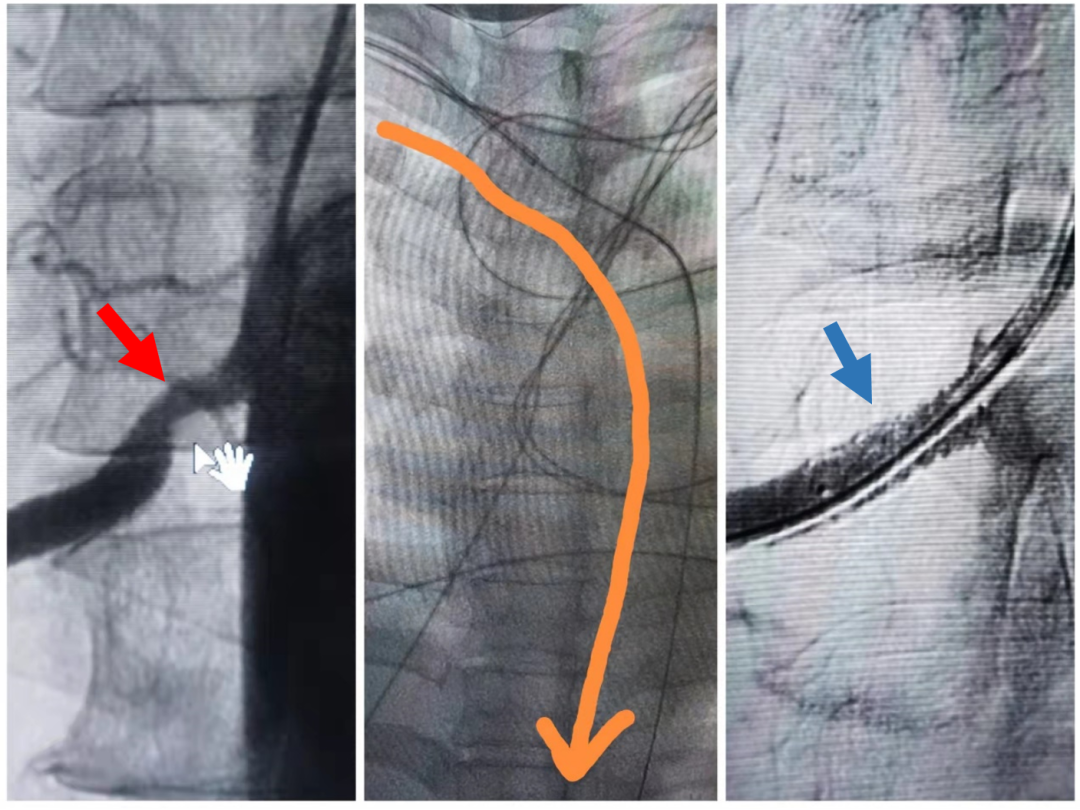

右侧肾动脉起始段重度狭窄(红箭头),桡动脉至肾动脉入路(中间图像),支架术后造影显示肾动脉显影良好,无残余狭窄(蓝箭头)

入院后头颈CTA提示右侧椎动脉起始段中-重度狭窄;肾动脉彩超提示右侧肾动脉重度狭窄。经桡动脉入路行全脑血管造影提示:右侧椎动脉开口处中度狭窄;肾动脉造影提示:右侧肾动脉起始段重度狭窄(狭窄率约75%),前向血流减慢,远端分支显影差。

椎动脉狭窄未达手术指征,但肾动脉严重狭窄是导致高血压及高血压性脑出血的“元凶”,必须予以手术解决。经患者及家属充分同意后,同期经桡动脉入路行右侧肾动脉支架置入术,手术过程顺利,支架置入过程历时仅20分钟,术中术后无不良反应,术后血压稳定。